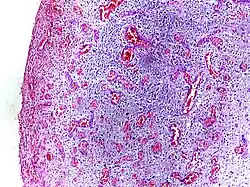

- Fibrinous inflammation: Inflammation resulting in a large increase in vascular permeability allows fibrin to pass through the blood vessels. If an appropriate procoagulative stimulus is present, such as cancer cells,[9] a fibrinous exudate is deposited. This is commonly seen in serous cavities, where the conversion of fibrinous exudate into a scar can occur between serous membranes, limiting their function. The deposit sometimes forms a pseudomembrane sheet. During inflammation of the intestine (pseudomembranous colitis), pseudomembranous tubes can be formed.